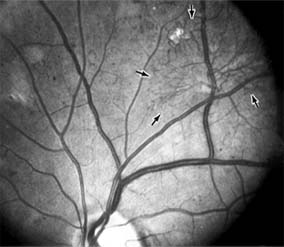

Figure 10-23

Figure 10-23: Fluorescein angiogram shows hypofluorescence from capillary drop-out (arrows) typical of ischemic diabetic maculopathy.